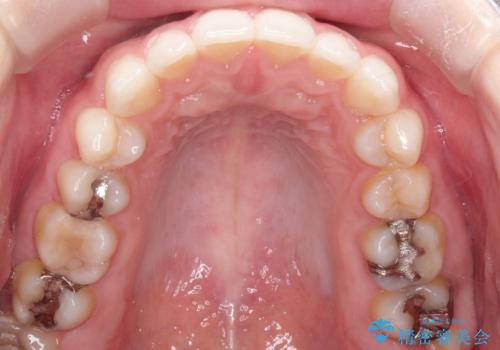

使用時間を守っていただけたので、スムーズに治療を終わることができました。

1周目が終わり、かなり綺麗になりましたがもう少し納得出来るまで続けたいという要望に答えてくださり、今2周目を終え本当に満足いく結果になりました。ありがとうございます。矯正を通して歯は意外と簡単に動くのだなと身をもって感じたのでこれからもリテーナーを怠らずつけ続けたいと思います。